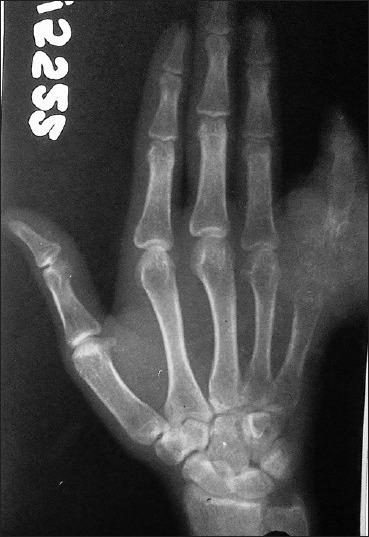

Rhinosporidiosis is a chronic granulomatous disease caused by Rhinosporidium seeberi. It usually affects the mucocutaneous tissue of the nose. Bone involvement is rare. We report a case of Rhinosporidiosis of the nasopharynx which later involved the right little finger where ray amputation was performed.